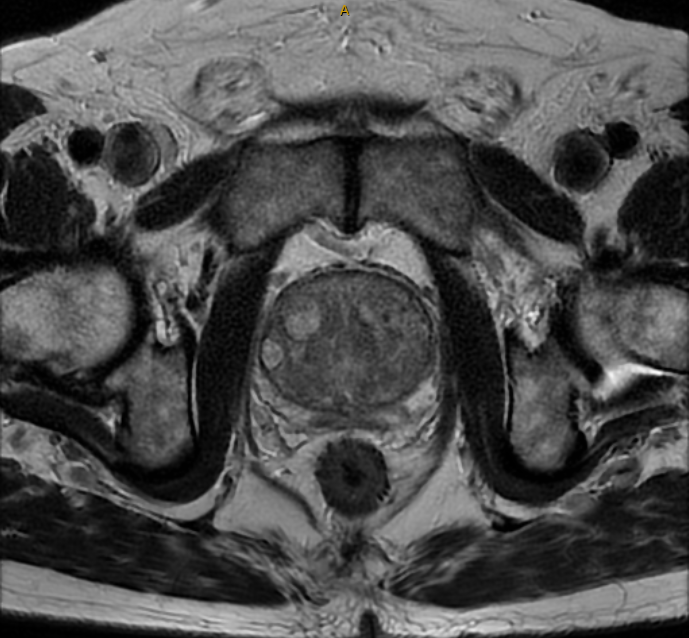

Prostate cancer is the main contraindication for PAE. This is screened for with a prostate MRI prior to all PAE procedures.

If embolisation is considered appropriate, prostate MRI and high-quality CT angiography will be required to evaluate pelvic vasculature and confirm candidacy. Left arm vasculature will also be assessed.